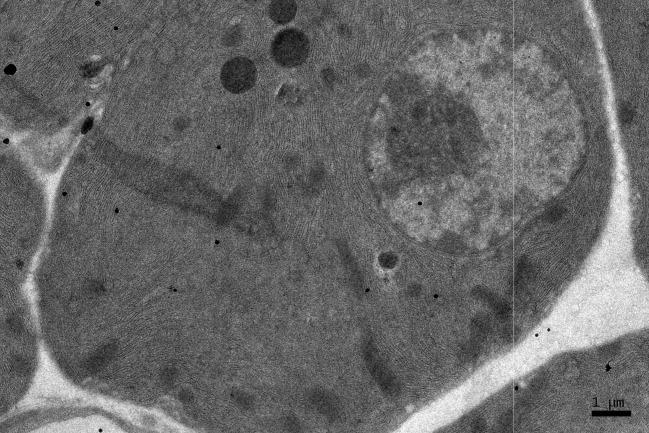

Electron Microscopic Radioautographic Study on the Protein Synthesis in the Pancreas of Aging Mice With Special Reference to Mitochondria.

We studied 10 groups of mice during development aged from fetal day 19 to postnatal month 24. They were injected with H-leucine, a precursor for protein synthesis, sacrificed and the pancreatic tissues were taken out, fixed and processed for light and electron microscopic radioautography. On many radioautograms the localization of silver grains demonstrating protein synthesis in pancreatic acinar cells in respective aging groups were first analyzed qualitatively. Then the number of silver grains and the number of cell organelles in each cell in respective aging groups were analyzed quantitatively in relation to the aging of animals. The number of mitochondria, the number of labeled mitochondria and the mitochondrial labeling index labeled with silver grains were counted in each pancreatic acinar cell.

The number of silver grains in cell nuclei and cell organelles changed with the aging of animals. The number of mitochondria, the number of labeled mitochondria and the labeling indices showing protein synthesis at various ages increased from embryonic day 19 to postnatal newborn day 1, 3, 7, 14, to young adult month 1, and 2, reaching the maxima, then decreased at old adult month 6 and senile year 1 to 2, indicating the aging changes.